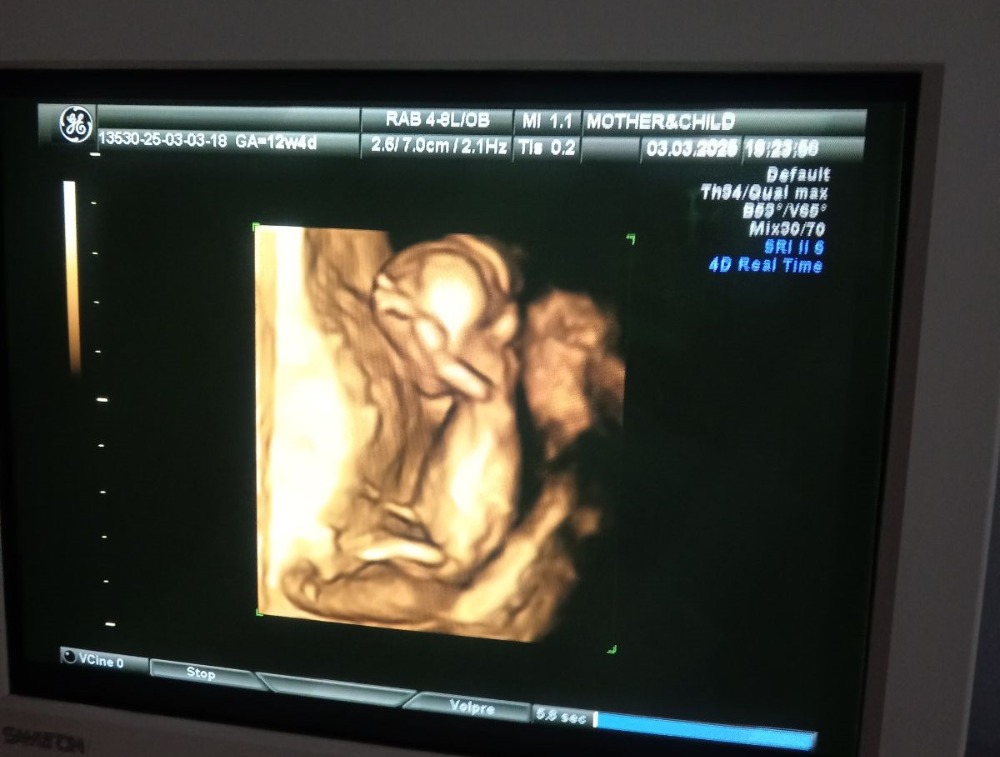

Чашка утреннего кофе, добрый день! 🌷а это фото сегодня делали)) на кого похож?)) Изображение

Lena Sorokina, скорее на девочку, но видно не очень хорошо.

Чашка утреннего кофе, ну значит еще одна принцессочка будет 🌷

Всем привет, девочки, может увидите кто тут у нас) Изображение

Девочка